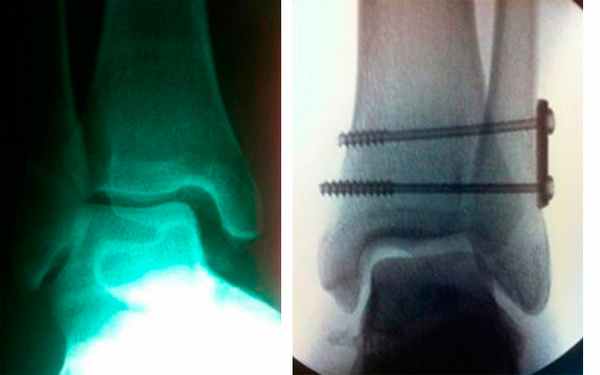

(Справа) При МРТ в аксиальной плоскости на ППВИ в режиме FS визуализируется частичная консолидация перелома «задней лодыжки». Наблюдаются разрыв ПНМСЕЗ и латеральная ротация малоберцовой кости в малоберцовой вырезке. Наличие медиально периостальной реакции свидетельствует о разрыве дельтовидной связки (не показана). (Слева) При рентгенографии голеностопного сустава, выполненной в проекции суставной щели, определяется состояние после остеосинтеза перелома малоберцовой кости типа С по Веберу и перелома медиальной лодыжки. Видно, что был установлен синдесмозный винт. Наблюдается стабильное расширение синдесмоза: глубина перекрытия теней костей составляет (Справа) У этого же пациента при КТ в аксиальной плоскости в синдесмозе визуализируется костный фрагмент, который препятствовал выполнению закрытой репозиции. Фрагмент пришлось удалить и провести открытую репозицию. КТ позволяет установить причину неэффективности репозиции. (Слева) При МРТ в коронарной плоскости на Т2ВИ в режиме FS определяется смещение кверху разорванной ПНМС. Синдесмоз расширен. Наблюдается частичный разрыв волокон глубокого слоя дельтовидной связки.

На рентгенограмме в переднее-задней проекции основными проявлениями недостаточности синдесмоза являются расширение вилки голеностопного сустава, расширение медиальной суставной щели и наклон таранной кости во фронтальной плоскости, травматическая эрозия плафона большеберцовой кости. Задний вывих малоберцовой кости в дистальной части голени виден, как заднее смещение малоберцовой кости относительно большеберцовой кости. Делают рентгенограммы с внутренней и наружной ротацией голени на которых имеется асимметрия суставной щели, расширение вилки голеностопного сустава, смещение наружной лодыжки назад и наклон таранной кости. Синдесмоз может оказаться поврежденным при отсутствии рентгенологических изменений. Самым информативным методом, который позволяет рассмотреть состояние отдельных связок, выявить дефект синдесмоза и определить соотношение костей голени является МРТ.

Хирургическую операцию делают при разрыве предней и задней связок межберцового синдесмоза, разрыве связок с расхождением берцовых костей более 2 мм, разрыве связок с нарушением функции голеностопного сустава. При остром повреждении синдесмоза, который дает нестабильность, делают операцию, в ходе которой репонируют малоберцовую кость в вырезку большеберцовой и фиксируют кости винтом. При разрыве синдесмоза в сочетании с переломом берцовых костей и переломо-вывихом голеностопного сустава делают остеосинтез обеих берцовых костей и фиксацию синдесмоза путем стяжки вилки голеностопного сустава. При хронической нестабильности, вызванной разрывом синдесмоза, делают такие операции, как реконструкция передней, задней и межкостной связок синдесмоза, тенодез короткой малоберцовой мышцы, аутопластику трансплантатом из сухожилия длинной малоберцовой мышцы, аллопластику с помощью синтетических связок. После вмешательства накладывают гипсовую иммобилизацию. Для восстановления целостности синдесмоза делают операцию фиксацию межберцового синдесмоза винтами или стягивают берцовые кости с помощью связки. Кости временно свинчивают с помощью компрессионного винта на 6 недель. Нога находится в гипсовой повязке в течение 3 недель. После снятия гипса на ногу надевают ортез или тутор. Тутор ограничивает движения стопы в сагиттальной плоскости и оказывает компрессионное воздействие на лодыжки. Благодаря давлению на берцовые кости с двух сторон поддерживается необходимое расстояние между ними, что способствует срастанию связок синдесмоза.

Рис. 8. Устранение разрыва межберцового синдесмоза после операции фиксации винтами